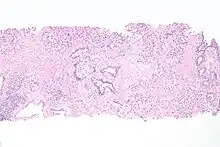

| Histopathology of transitional carcinoma of the urinary bladder. Transurethral biopsy. Hematoxylin and eosin stain. | |

Histopathology of urothelial carcinoma of the urinary bladder, showing a nested pattern of invasion. Transurethral biopsy. H&E stain